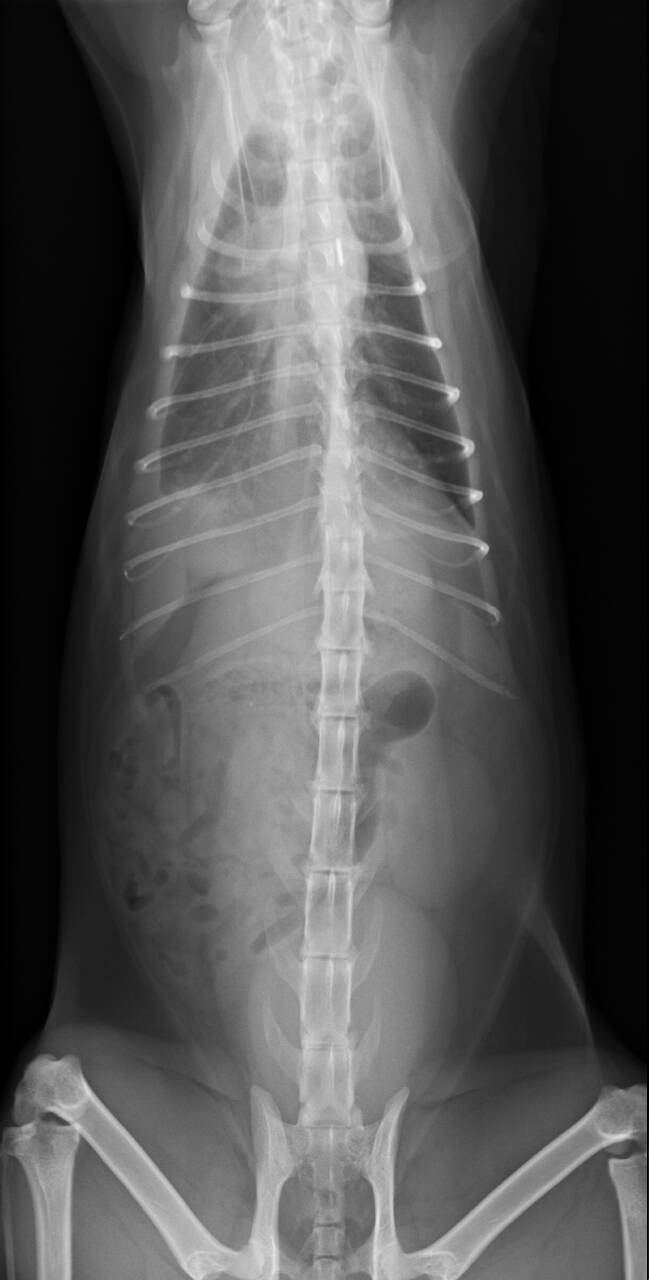

長青醫師詳細觸診、血檢、X光、超音波、抽胸水檢驗(下午約抽出18ml)、眼球葡萄膜炎檢測。

血液檢驗跟胸水檢驗都有發現不正常細胞(病菌),必須再更進一步檢查膿胸的發生原因。

住院期間僅用抗生素治療未使用干擾素,胸水未再激增也未再急喘, 醫師逐一排除罹患腹膜炎及淋巴腫瘤的可能性, 確認為創傷性膿胸。